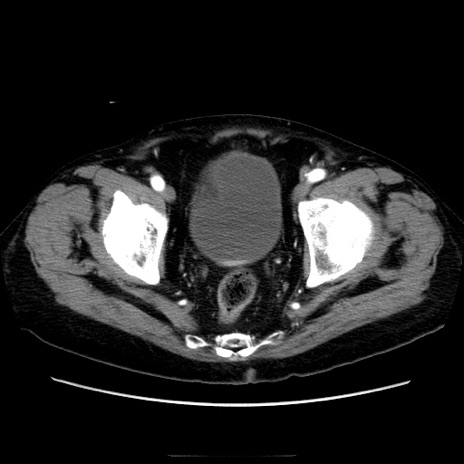

冠状断像

【症例】70歳代男性

【主訴】腹痛

【現病歴】肝硬変・肝細胞癌にてかかりつけの方。約9時間前に食後より腹痛出現。症状が徐々に増悪し、嘔吐出現したため来院。

【既往歴】肝硬変、肝細胞癌(RFA、TACE後)

【身体所見】意識清明、表情苦悶様、BT 36℃、BP 129/78mmHg、P 88bpm、SpO2 97%(RA)、右上腹部から心窩部にかけて圧痛あり、反跳痛なし、筋性防御あり。

【データ】WBC 5800、CRP 0.16